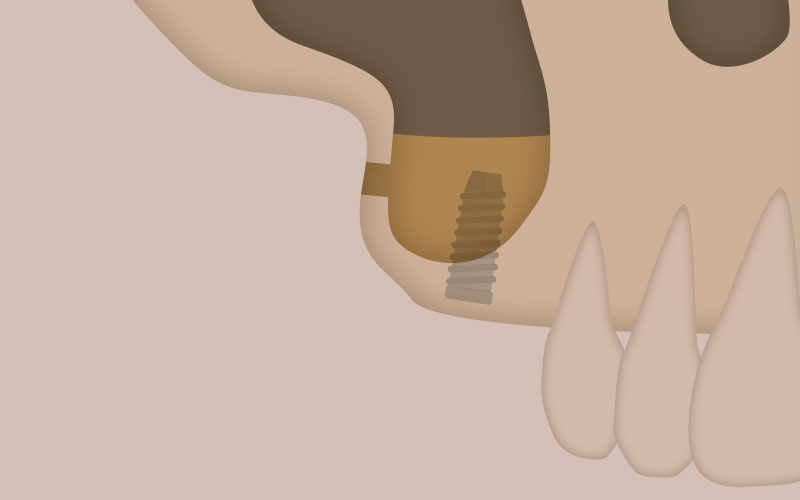

CASE.01

サイナスリフト

上顎の骨の上には(上顎洞)と呼ばれる大きな空洞があります。上顎の奥歯がを失った状態のままだと、時間の経過とともにこの空洞が拡がり、インプラントを埋入するのに必要な上顎の骨の厚みが足りなくなります。そこで、上顎洞に骨を移植したり骨補填材(骨を増やす材料)を用いて、上顎洞の底部分を押し上げてできたスペースに骨の厚みを作る処置です。

CASE.02

ソケットリフト

上顎の骨の上には(上顎洞)と呼ばれる大きな空洞があります。上顎の奥歯がを失った状態のままだと、時間の経過とともにこの空洞が拡がり、インプラントを埋入するのに必要な上顎の骨の厚みが足りなくなります。そこで、上顎洞に骨を移植したり骨補填材(骨を増やす材料)を用いて、上顎洞の底部分を押し上げてできたスペースに骨の厚みを作る処置です。